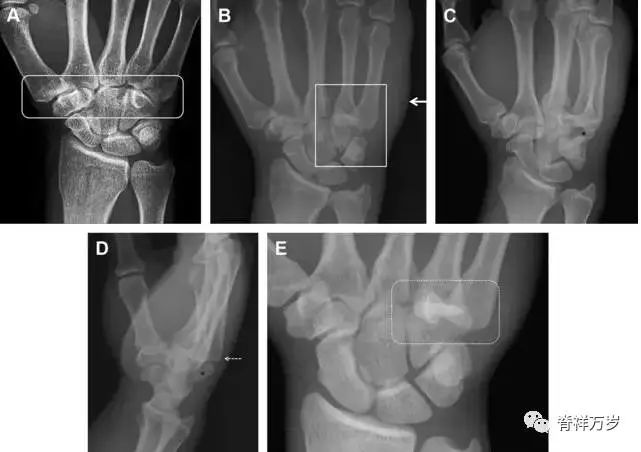

33.腕掌关节骨折脱位

腕掌关节骨折脱位为高能量损伤,常伴有神经损伤。腕掌关节组成骨多,侧位片上重叠遮挡多,骨折不易发现,容易漏诊。在前后位片上,关节面不平滑、关节间隙不对称、关节皮质破坏、关节面重叠常提示腕掌关节骨折脱位。特别是第 4、5 腕掌关节脱位,在前后位片上不容易发现;该损伤不稳定,也称为「变异型拳击手损伤/骨折」。

图 4 第 4、5 腕掌关节骨折脱位。(A)正常腕掌关节,关节面平衡起伏、平行;前后位(B)、斜位(C)、侧位(D),第 5 掌骨近端附近软组织肿胀(白色箭头),冠状面关节面重叠,背侧撞击剪切应力致钩状骨骨折(*),在前后位及斜位片上可见双密度影。第 4 掌骨底部可见微小骨折碎片(D,虚线箭头),第 4、5 掌骨掌侧成角。(E~G)变异型拳击手损伤:第 4、5 掌骨背侧脱位而未见骨折(E,虚线方框),钩状骨有骨折小碎片(F,短虚线箭头),第 4 掌骨基底部关节内骨折(G,长虚线箭头)。